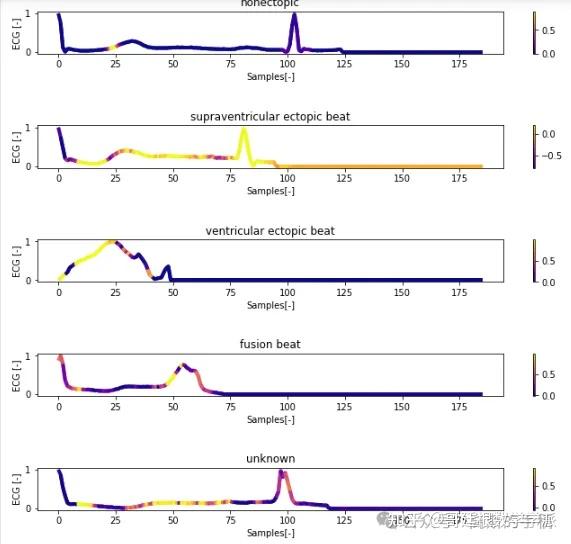

一维神经网络的特征可视化分析-以心电信号为例(Python,Jupyter Notebook)

包括Occlusion sensitivity方法,Saliency map方法,Grad-CAM方法